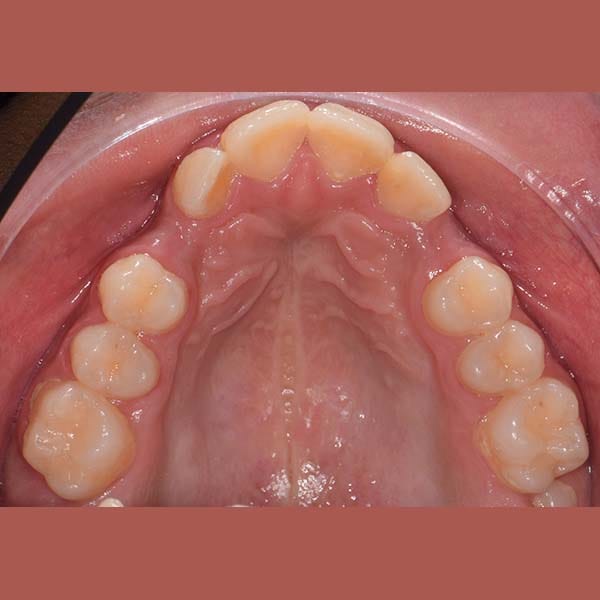

This girl suffered from severe upper jaw stenosis, which negatively affected her smile,

suppressed the beauty of her white teeth when smiling, and also led to a buried upper-right canine in the bone, and a reverse bite in the back teeth.

We have treated her by means of Daimon braces without any tooth extraction and opened a space for the buried canine to stand in its proper position. In the end, our little friend gained a wide and beautiful smile.